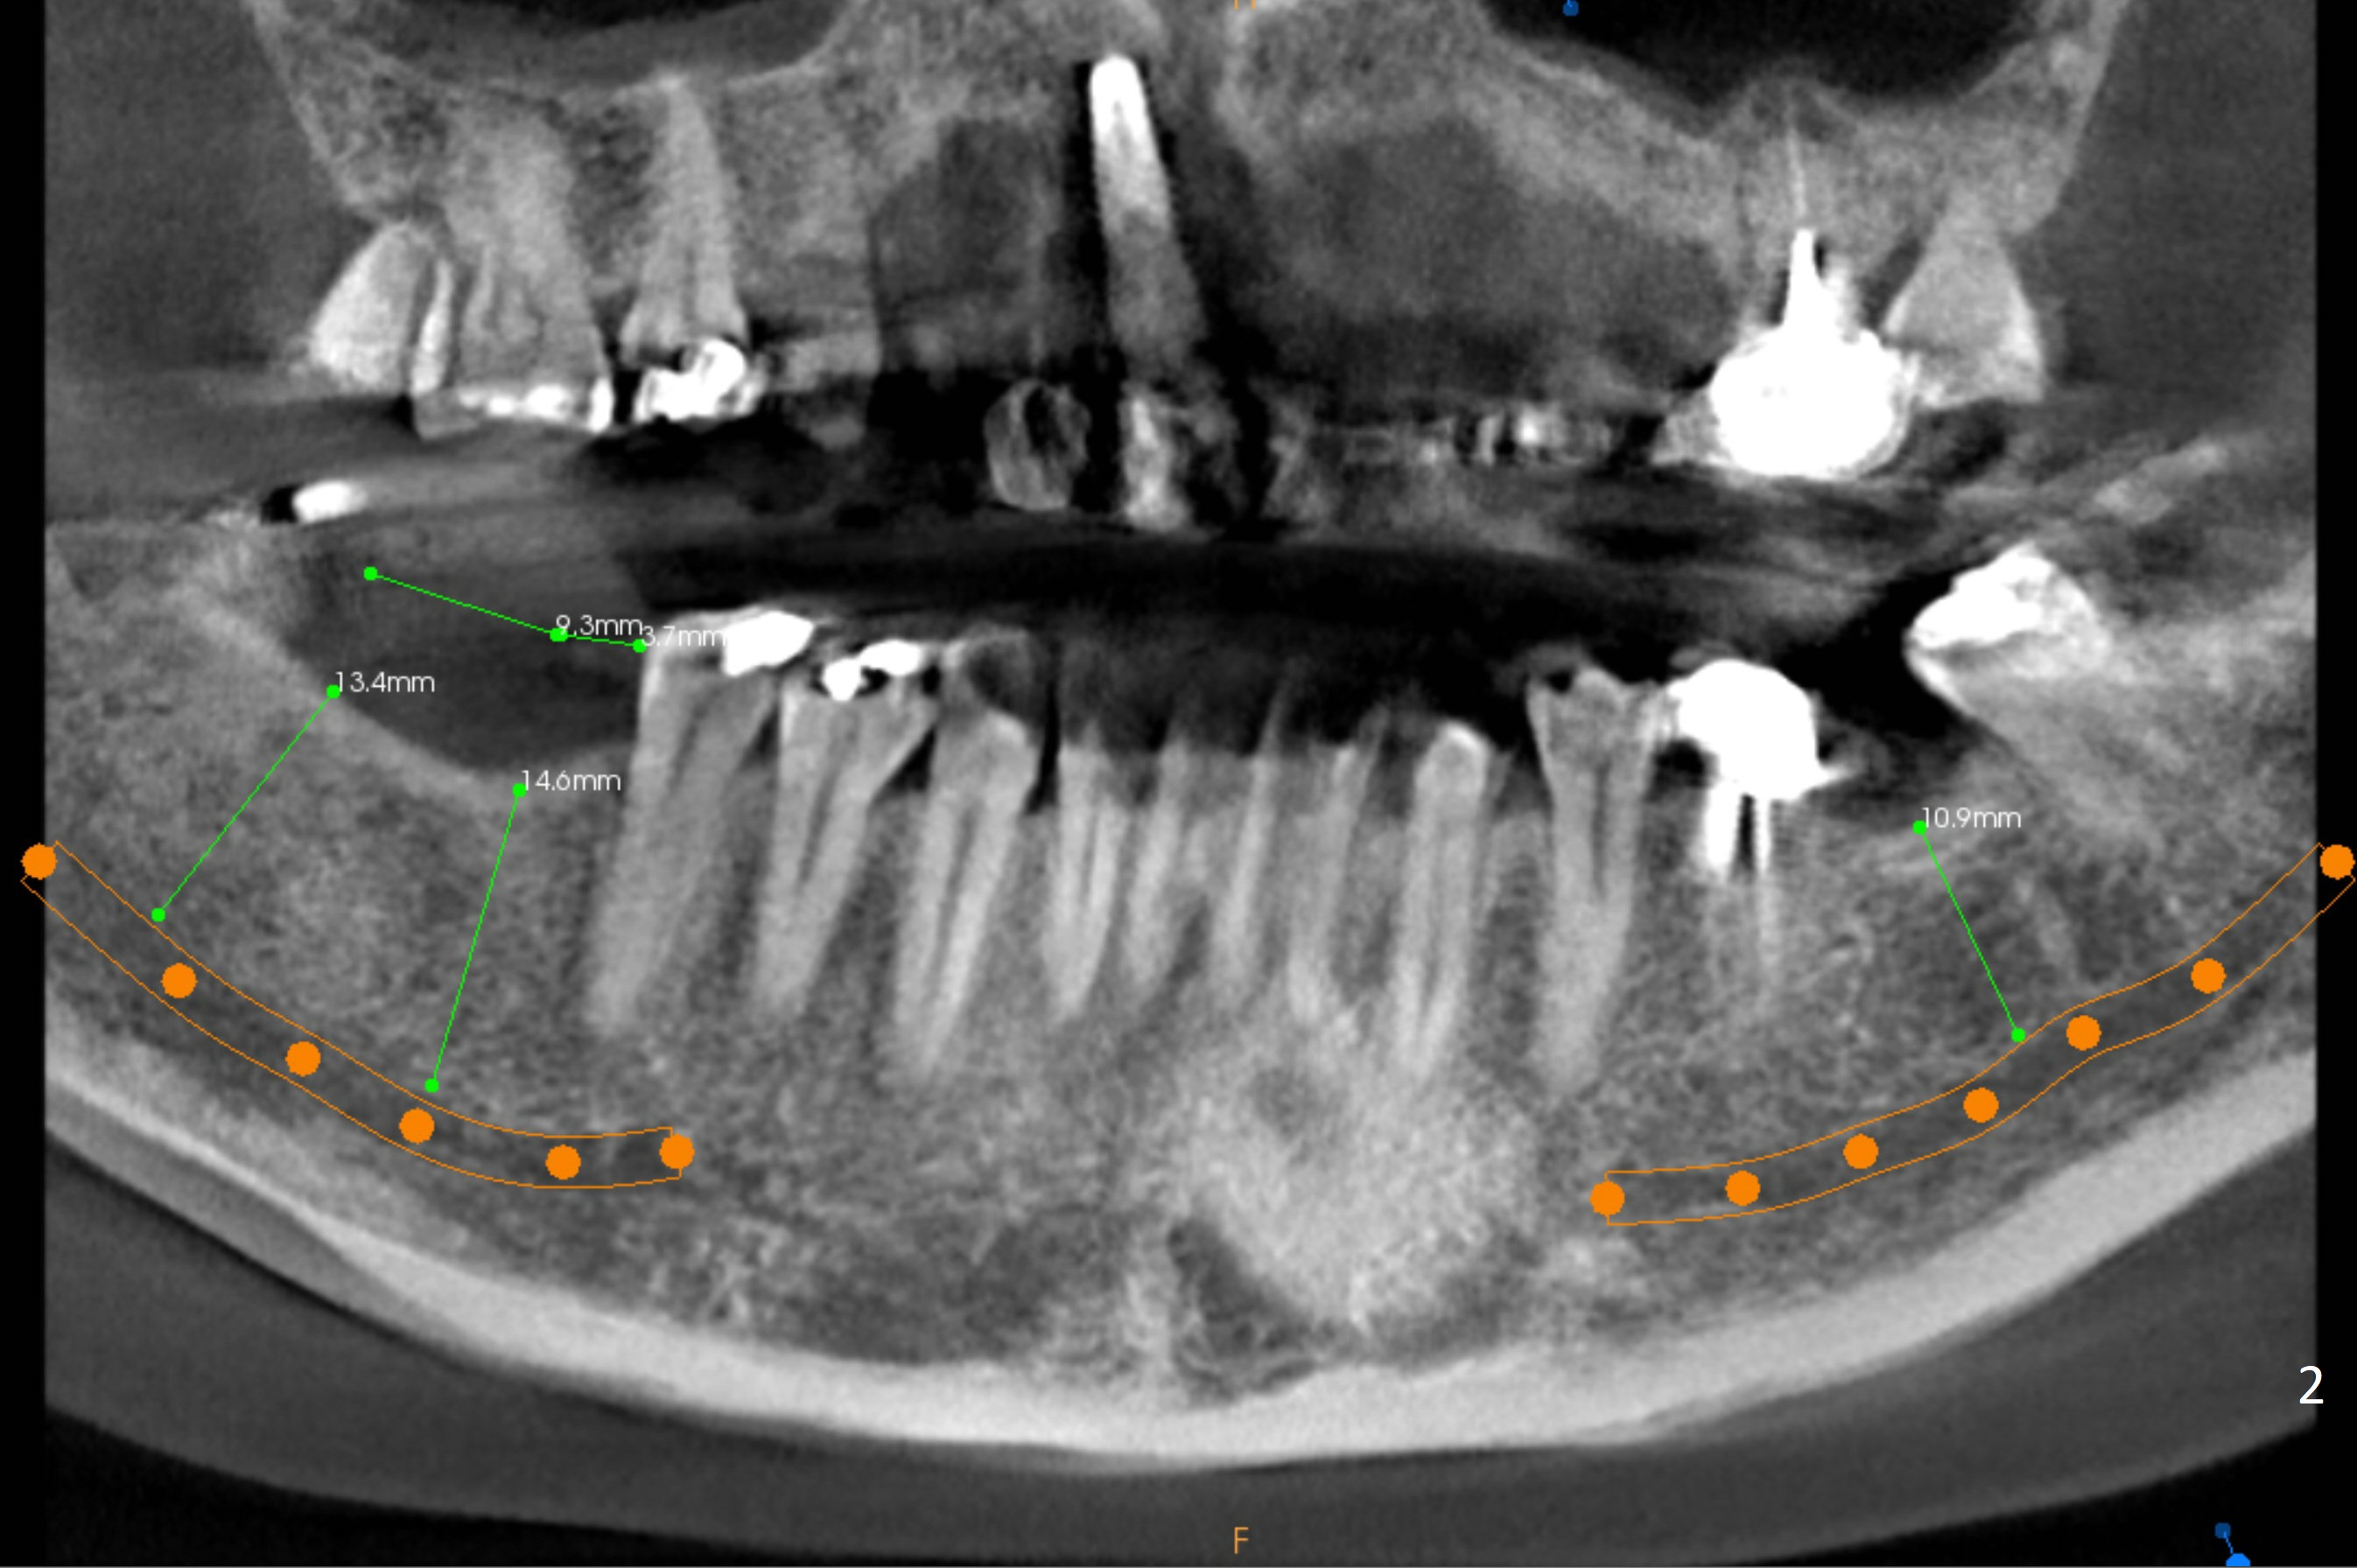

A healthy 37-year-old woman has 3 missing lower molars (Fig.1 panoramic view from CBCT). She has had implants at #8 and 10. The bone height for these molars is shown in Fig.2. The 1st molar ridges appear to be narrow (Fig.4,5,6), as compared to that of the 2nd molar (Fig.3 (B: buccal)). Ridge reduction seems to be necessary for the 1st molar sites prior to implant (green area) placement or deeper osteotomy.